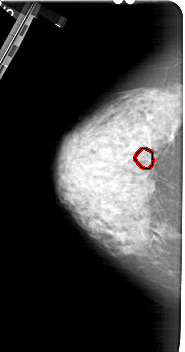

A_1282_1.LEFT_CC

LEFT_CC LINES 5266 PIXELS_PER_LINE 2761 BITS_PER_PIXEL 12 RESOLUTION 43.5 OVERLAY

FILE: A_1282_1.LEFT_CC.OVERLAY

TOTAL_ABNORMALITIES 1

ABNORMALITY 1

LESION_TYPE MASS SHAPE ARCHITECTURAL_DISTORTION MARGINS SPICULATED

ASSESSMENT 4

SUBTLETY 1

PATHOLOGY BENIGN

TOTAL_OUTLINES 1

BOUNDARY